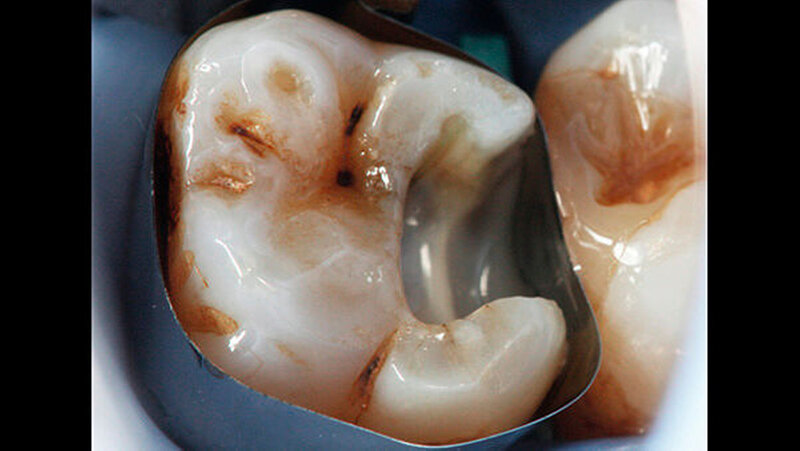

-Schnee war positiv. Die Behandlung wurde auf Wunsch des Patienten ohne Lokalanästhesie durchgeführt. Vor der Präparation erfolgte das Anlegen von Kofferdam an den Zähnen 24 bis 27. Zunächst wurde mit rotierenden Diamantschleifern unter Wasserkühlung von okklusal ein Zugang zum Defekt geschaffen. Der distale Kavitätenbereich wurde mit oszillierenden Instrumenten präpariert (SonicFlex, KaVo) (Abbildung 2). Dabei wurde die Kavität so zierlich wie möglich gestaltet.

Anschließend erfolgte die Kariesexkavation mit Rosenbohrern unter optischer Kontrolle mit einem OP-Mikroskop. Die Kavität wurde im Verlauf der Exkavation mehrmals mittels FACE (fluoreszenzgestützter Kariesexkavation, SIROinspect, Sirona) auf Residualkaries überprüft [Buchalla W et al., 2013].